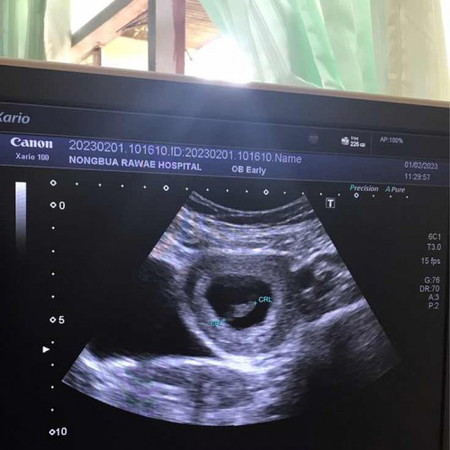

อัลตราซาวด์8สัปดาห์2วัน

วันนี้ไปฝากครรภ์ ได้เจาะเลือด และซาว ดีใจมากที่เห็นตัวอ่อน และได้ฟังเสียงหัวใจน้อง เสียงเบามาก หมอบอกน้องกำลังสร้างหัวใจ ดีใจแบบบอกไม่ถูก❤️🤰👩❤️💋👨👨👩👧

วันนี้ไปซาวด์มาเหมือนกันค่ะ ของแม่น้องกี่ซม.คะ ของเราหมอบอกน้องตัวเล็กไป1weekอาจจะคลาดเคลื่อน แต่กังวลใจมาก